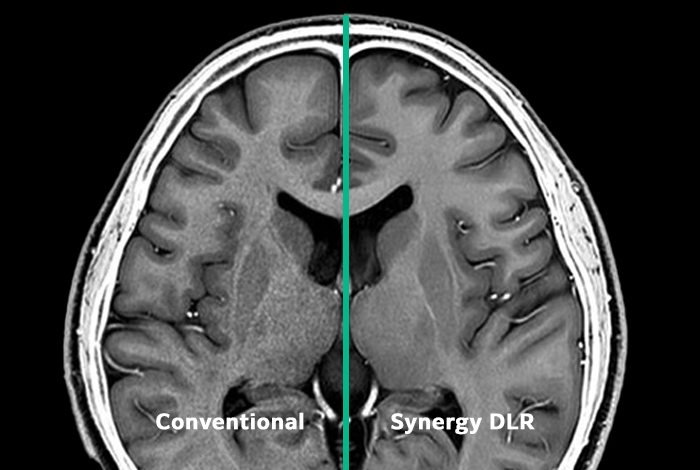

Synergy Deep Learning Reconstruction (DLR) optimizes image quality and minimizes scan time, delivering brain exams that demonstrate our commitment to excellent image quality.

Synergy DLR, a Deep Convolutional Neuro Network reconstruction engine, enhances SNR for fast, clear imaging. Combined with workflow-engineered RF coils, open-sided architecture, and unique lateral table movement, it provides speed, quality, and comfort for patients, technologists, and radiologists.